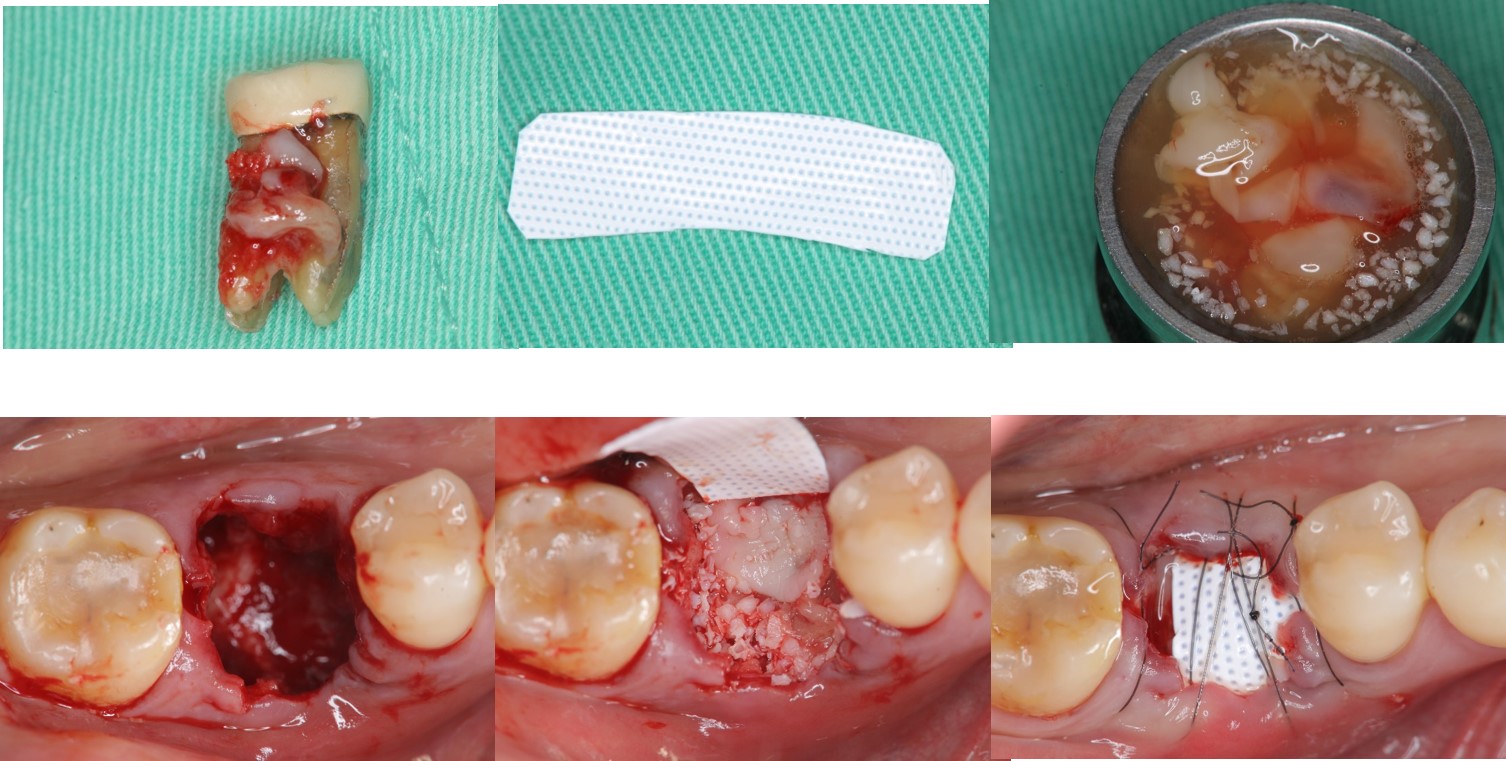

拔牙同時補骨